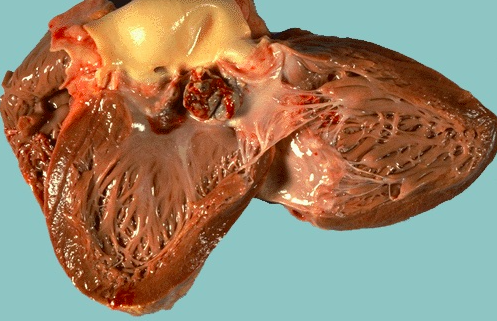

- This is the left ventricular wall which has been sectioned lengthwise to reveal a large recent myocardial infarction

- The center of the infarct contains necrotic muscle that appears yellow-tan

- Surrounding this is a zone of red hyperemia

- Remaining viable myocardium is reddish- brown.